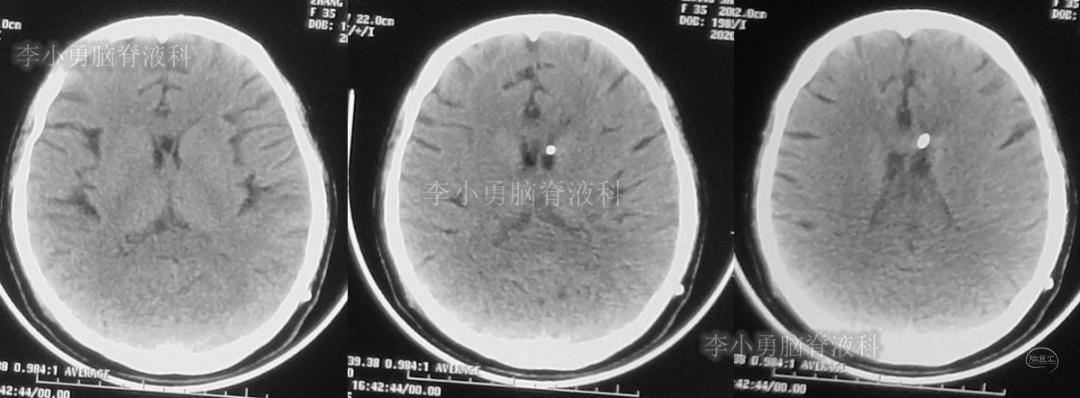

患者于2018年1月29日,突发头痛、头晕、恶心、呕吐,并高热40度。在当地医院门诊输入4天抗生素后发热缓解,但出现了双眼不能上视(眼球不能向上看)。5天后即2018年2月3日,在当地的第1家医院:浙江省海宁市某医院行头颅CT(图-1)发现脑室扩张,当地医院诊断为“梗阻性脑积水”。

图-1:2018年2月3日头颅CT